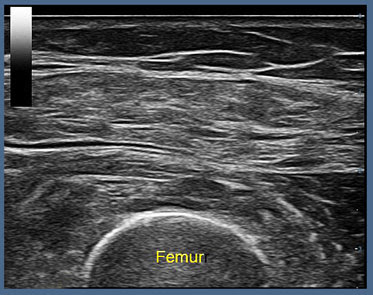

Scan #1 of 7: PRE-TREATMENT SONOGRAM (Pre Quad) 8/18/2023 12:59:49pm

This preflight stage is a pre-treatment review using medical-grade ultrasound probe at 14 MHz frequency with 12 cm penetration and axial resolution of 0.5 mm. Conducted is a transverse scan of the quadriceps muscle. The top set of lines (labeled subcutaneous tissue). Right underneath the firm, fascia is located and between the subcutaneous fascia and the curved white bony femur outlined on the bottom is the interdigitating muscle tissues that form the four tendons of the quadriceps near the patella.